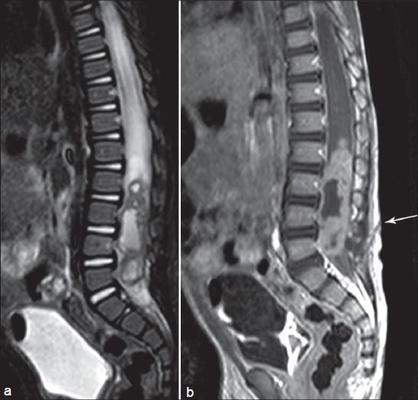

Manyetik Rezonans (MR) cihazları iyonizan radyasyon oluşturmazlar. Oluşturdukları manyetik alan sayesinde görüntü oluşturan bu cihazlar yüksek rezolusyonda anatomik detay verirler. MR cihazında hastanın içine yattığı tünel olan ve magnet adını verdiğimiz büyük bir parça vardır. Bu tünel içerisine yatan hastanın incelenecek bölgesine coil adını verdiğimiz alıcılar bağlanır ve incelemeye bundan sonra başlanır. MR cihazı ile bütün insan vücudu görüntülenebilir. Özellikle beyin ve omurilik hastalıklarında, ortopedik hastalarda özellikle eklem değerlendirmesi için sıklıkla kullanılır. MR görüntüleme teknolojisi de yıllar içinde inanılmaz bir ilerleme göstermiştir.

Difüzyon MR, MR spektroskopi, Perfüzyon MR, MR traktografi gibi ileri düzey MR incelemeleri yapılmaya başlanmıştır. Diffüzyon ve perfüzyon MR ile beyin enfarkt ve kanamalarının erken tanısı, spekroskopi ile kitlelerin ayırıcı tanısı, MR traktografi ile de beyin cerrahisi geçirecek hastaların operasyon sonrasında nasıl etkileneceği önceden saptanabilmektedir. Ayrıca fonksiyonel MR incelemeleri de bir hayli gelişmiş olup; eklemlerin hareketli görüntüleri alınabilir ya da beyin kitlesi olan hastalarda yapılacak operasyonun motor kortekse hasar vermemesine dikkat etmek için kullanılabilir. Mamografi incelemesi yapılamayacak hastalarda ( büyük meme kistleri, meme protezi olan hastalarda) ya da meme kanseri cerrahisi geçirmiş hastaların takibinde Meme MR kullanılır. Gebe hastalarda gerekli durumlarda MR görüntüleme yapılabilir. Ancak ilk trimesterde yani gebeliğin ilk 3 ayında MR görüntülemenin güvenilirliği henüz kanıtlanmış olmayıp bu dönemlerde acil gereklilik olması koşuluyla ancak bu inceleme yapılabilir.